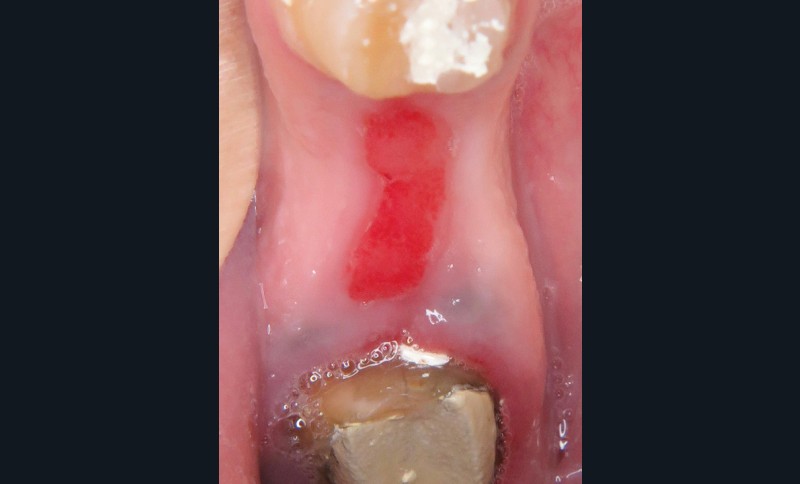

1. Épulis inflammatoire (plasmocytaire)

- Nodule indolore, pédiculé, érythémateux, parfois ulcéré (fig. 1a).

4. Épulis postextractionnel

- Granulome intra-alvéolaire à la suite d’une avulsion dentaire (fig. 4a et b).

- Absence de cicatrisation spontanée.